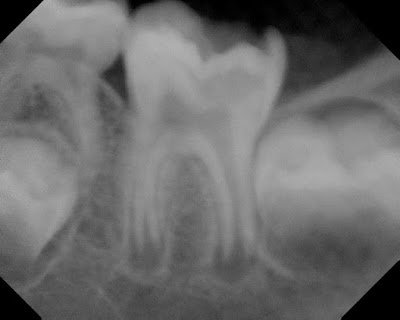

2 year recall reveals a symptomatic tooth with full function. Roots have continued to develop to normal length and thickness. Coronal protection recommended.

3 year recall finds tooth a symptomatic and functional. Root development is complete and appears normal.